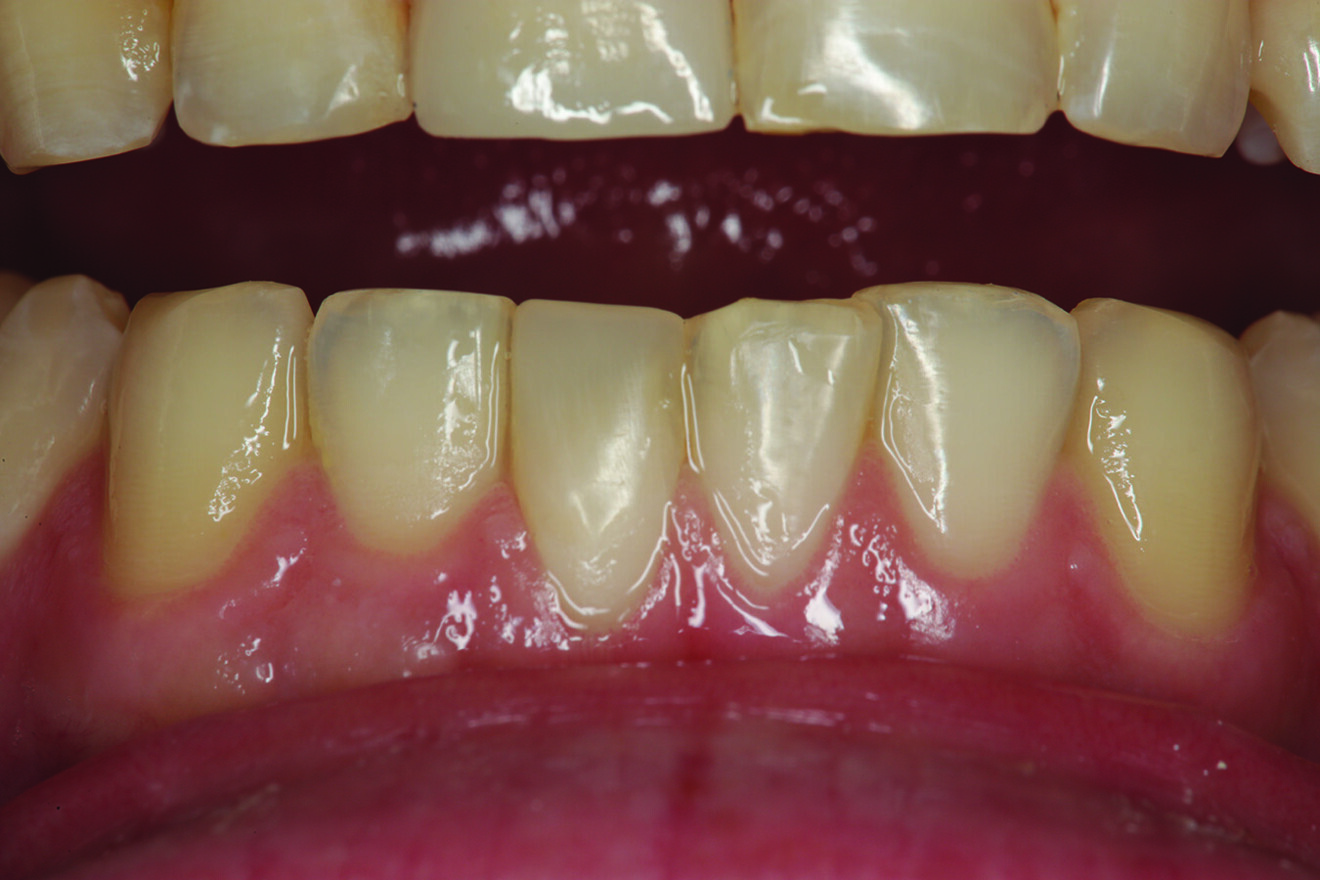

Fig. 14: Retracted facial view of tooth #11 after provisionalisation with the teeth in maximum intercuspation.